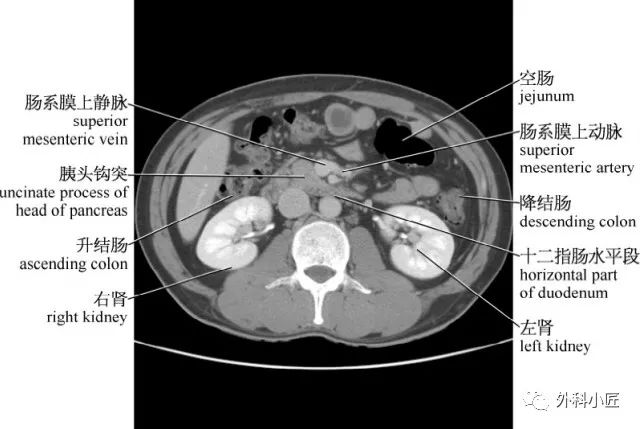

「腹部ct断层解剖」腹部ct扫描横断位解剖 详细标注,值得收藏